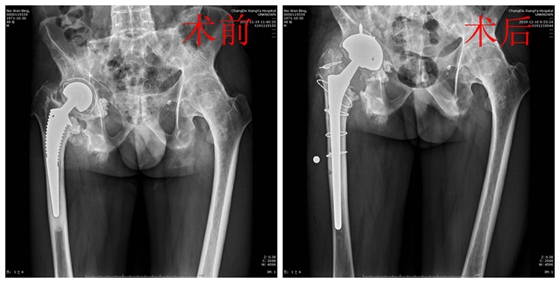

骨科主任张朝跃教授就聂先生的病情组织全科进行病例讨论。患者为强直性脊柱炎导致的左髋关节融合及右髋关节置换术后假体松动,两侧髋部均有手术指征。但考虑到其体质较差,手术时间长,出血较多,患者无法耐受,所以暂且行右髋关节翻修术。经过充分论证后,制定了周密的术前准备、手术方案以及应急预案。手术采用后外侧入路对周围组织分离保护,切开瘢痕化的关节囊,将关节脱位,行ETO截骨去除股骨假体后,装入生物型髋关节假体,C型臂透视下满意,假体固定可靠。经过3小时手术,成功为患者实施髋关节翻修手术。术后患者生命体征正常,髋部疼痛症状明显减轻,顺利出院。